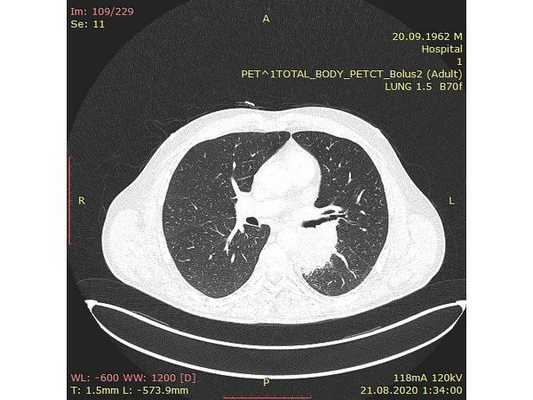

Чтобы провести первичное стадирование опухоли, пациенту проведена позитронно-эмиссионная томография в сочетании с компьютерной томографией (ПЭТ-КТ). По данным исследования, выявлена метаболически активная опухоль в корне левого лёгкого с бугристыми контурами размерами 41 х 43 мм. В толще опухоли проходят нижнедолевой бронх и бронх 6-го сегмента левого лёгкого, просветы бронхов значительно сужены. Нижняя доля левого лёгкого уменьшена в размерах за счёт того, что сегменты 6, 9 и 10 субтотально (частично) инфильтрированы и безвоздушны. Лимфатические узлы корня лёгкого и средостения не увеличены в размерах и не накапливают радиофармпрепарат (РФП), который был введён пациенту перед обследованием внутривенно. Других очаговых образований и очагов гиперметаболизма в организме не обнаружено.

При этом отмечено, что опухоль распространяется в средостение по нижней стенке левого главного бронха и широко прилежит к нижнегрудному отделу аорты (по заключению специалиста ПЭТ-КТ — имеется инвазия опухоли в ткани средостения и возможное врастание в стенку аорты). При самостоятельном пересмотре изображений отмечено, что "опухолевая" ткань, которая распространяется по нижней стенке левого главного бронха в средостение, не накапливает РФП (т. е. не является злокачественной), а стенка аорты в области "инвазии" опухоли имеет ровный чёткий контур и адвентициальную границу, что также свидетельствует об отсутствии онкологического процесса в этой области.